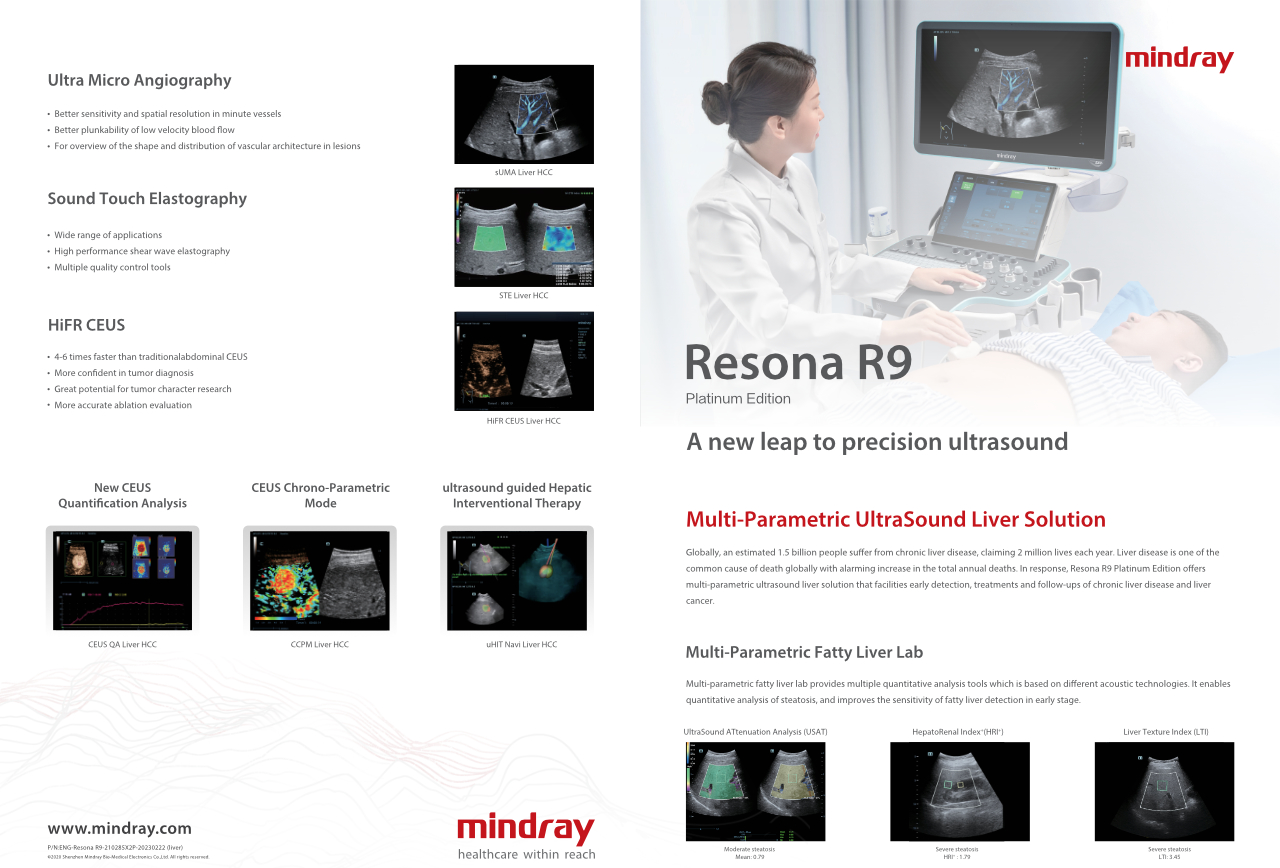

Bir karaci?er ne kadar net g?rĂŒlebilir?

Hemanjiyom veya karaci?er kanseri gibi fokal karaci?er lezyonlar? i?in, ultrason kontrast g?rĂŒntĂŒlemesi ?nemli bir rol oynar. Ultra geni? lineer olmayan UWN+ kontrast g?rĂŒntĂŒleme teknolojisi, daha dĂŒ?ĂŒk MI ve daha uzun perfĂŒzyon sĂŒresi g?zlemi ile daha iyi penetrasyon, daha yĂŒksek kontrast doku oran? elde edilmesine yard?mc? olabilir.